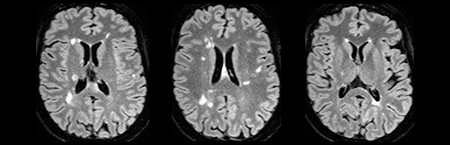

Ressonância magnética

• RM rebaseline e primeiro ano sem novas lesões T2 ou lesões captantes de gadolínio

• Aguarda RM 2º ano